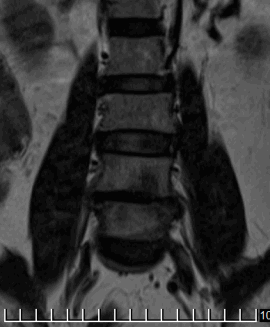

На МРТ в телах VL4-5 сигнал неоднородно снижен. Межтеловая щель сужена. Суставные поверхности неровные с узурацией, с краевыми остеофитами. Мягкие ткани вокруг инфильтрированы, утолщены, абсцессов нет. Спинномозговой канал сужен. За счет протрузии дисков VL4-5, VL5-S1 позвонков. Повышенный сигнал от тел остальных поясничных позвонков.

Рис. 2. МРТ при поступлении